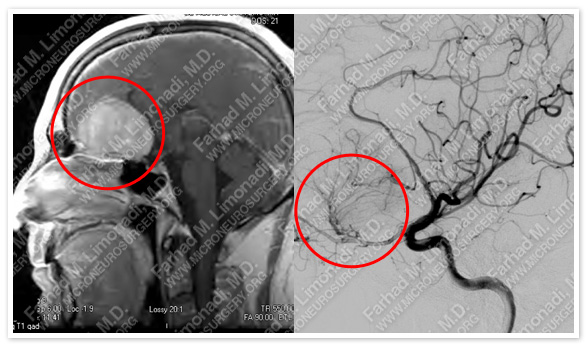

MRI scan of the patient’s brain shows a large olfactory groove tumor.

Cerebral angiography shows that this tumor is supplied by branches of the ophthalmic and anterior cerebral artery (right image).